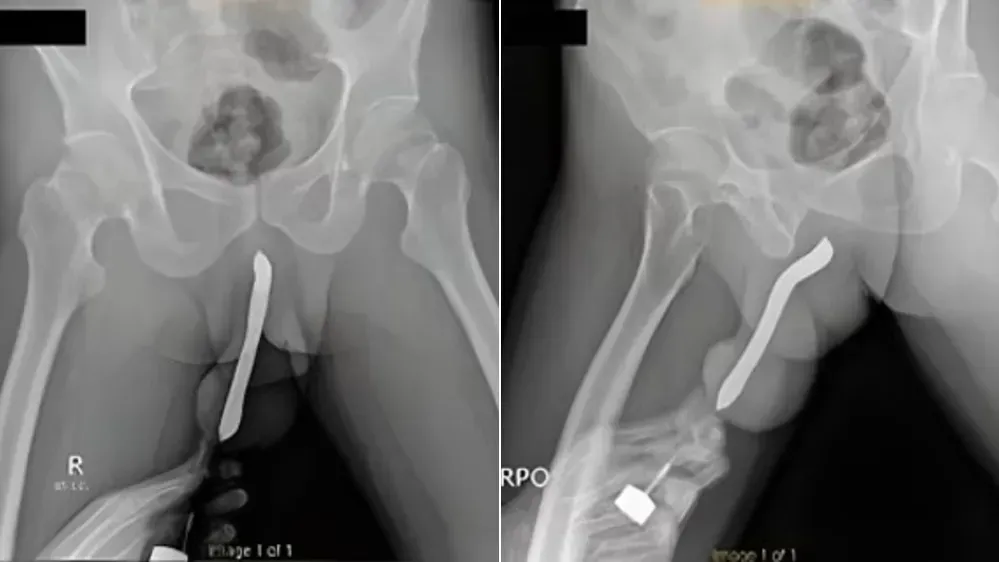

醫生動手術,替楊姓男子取出52年前的兒童牙刷。(互聯網)

安徽六旬男牙刷藏肚52年 以為會自然消化

• 印尼男為達到高潮陰莖開窿塞牙刷 激戰時下體骨折致腫如茄子

印尼男為達到高潮陰莖開窿塞牙刷 激戰時下體骨折致腫如茄子

• 西班牙21歲女食火雞鯁親 用20厘牙刷去撈反致整支卡喉嚨

西班牙21歲女食火雞鯁親 用20厘米牙刷去撈反致整支卡喉嚨